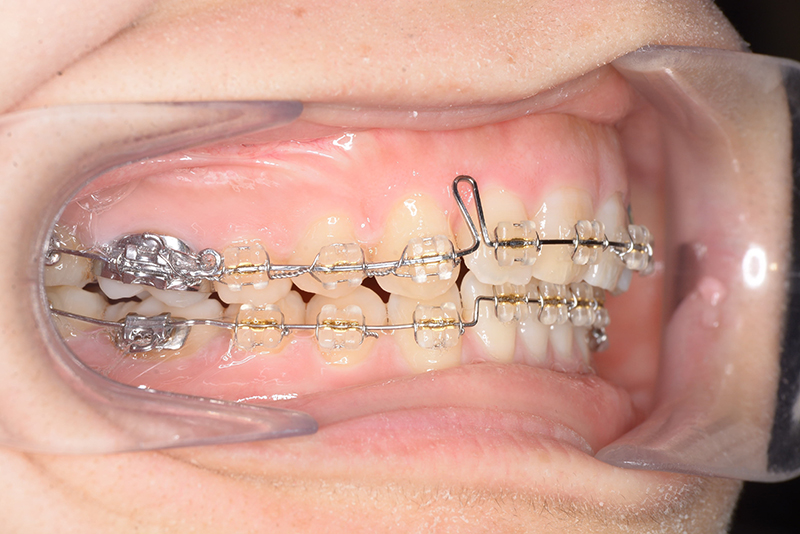

動的治療時(PLASによる上顎歯列遠心移動)

動的治療時

(PLASによる上顎歯列遠心移動)

IOP

口腔内所見 大臼歯、犬歯関係はⅡ級で、上顎中切歯は舌側傾斜しており、over jet1.5mm,over bite 6.0mmいわゆるⅡ級2類であった。

批評・予后 上顎臼歯は軽度に近心傾斜しつつ、歯列遠心部には奥行きがあり、下顎歯列には叢生は認められず、スピー湾曲も軽度であること。また軟組織上の問題もないため、上顎歯列の遠心移動による治療が妥当だと判断した。治療後において上顎歯列の遠心傾斜と共に下顎はカウンタークロックワイズローテーションをしながら咬合の緊密化が得られた。